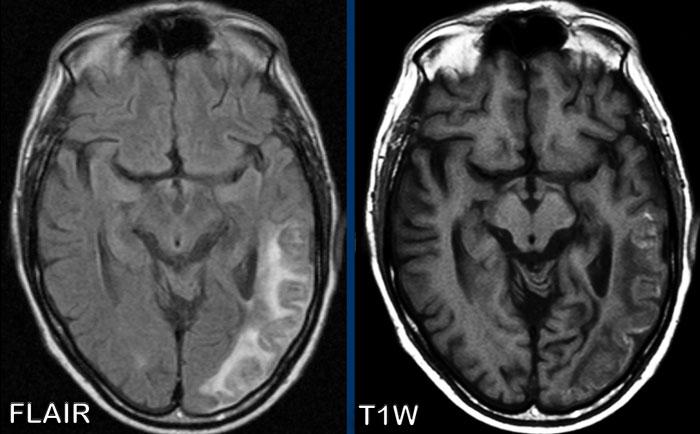

MS dạng khối u (Tumefactive MS)

Các hình ảnh này của một phụ nữ 50 tuổi, nhập viện với triệu chứng liệt nửa người bên trái (tay và chân). Không có tiền sử bệnh lý trước đó.

Hình ảnh

- Nhiều vùng tăng tín hiệu trên chuỗi xung FLAIR.

- Nhiều tổn thương ngấm thuốc dạng vòng. Vòng hở về phía ngoại vi.

- Trên DWI không có dấu hiệu hạn chế khuếch tán trung tâm trong lòng tổn thương, giúp loại trừ khả năng áp xe. Có một số hạn chế khuếch tán ở ngoại vi.

- Mặc dù các tổn thương khá lớn, không có dấu hiệu hiệu ứng khối và đây là đặc điểm điển hình của bệnh mất myelin như bệnh đa xơ cứng (MS).

Các dấu hiệu này điển hình cho MS dạng khối u (tumefactive MS).